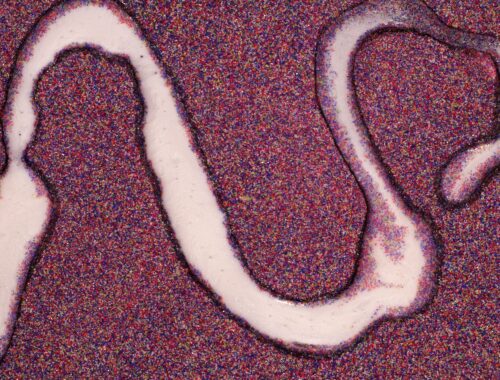

L’endométriose est une maladie chronique complexe, souvent accompagnée de fatigue, de troubles digestifs et de douleurs pelviennes. Mais parfois, ces symptômes persistent malgré les traitements, l’alimentation adaptée ou les approches naturelles. Et si, derrière ces manifestations, se cachait une autre…

Par Bertille 5 novembre 2025